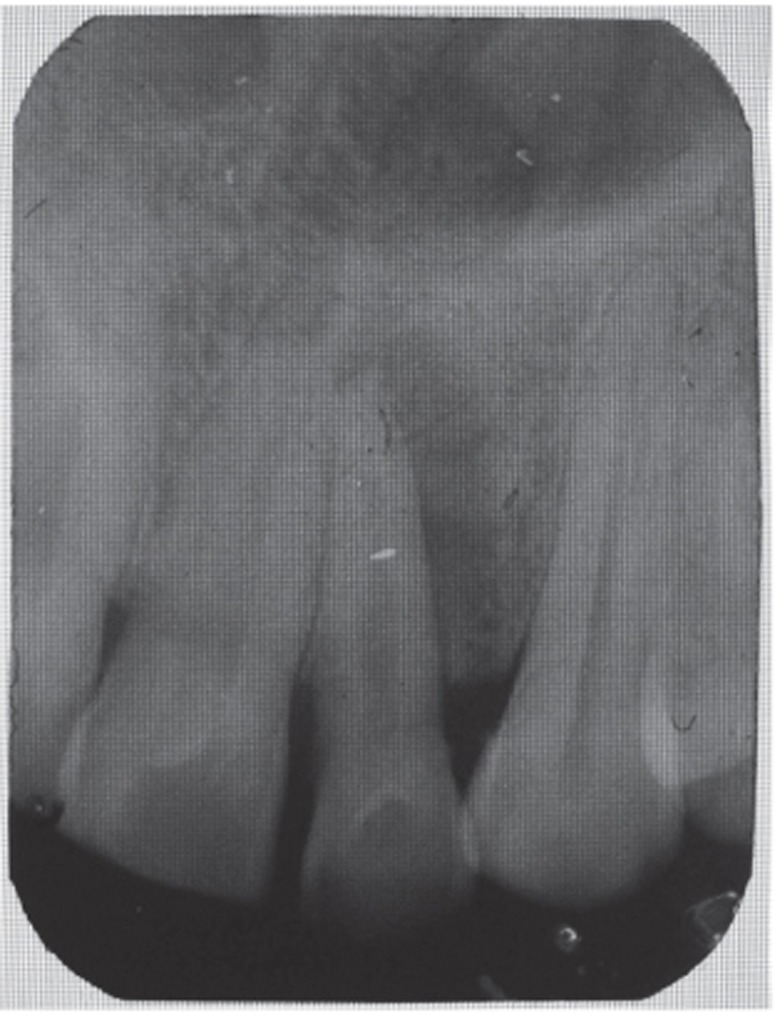

7). Closure of soft tissue flap was done with non resorbable black silk (3-0) suture using interrupted suturing technique. The sutures were removed 10 days after surgery. The patient was scheduled for regular recall intervals at 3, 6, 9 and 12 months. PRF and bone graft resulted in substantial amount of bone fill (

Figures 8a and 8b), and probing depth was reduced to 2 mm.

13 In the present case, it was observed that at 3, 6, 9 and 12 months follow-up after the surgical treatment of large chronic periapical lesion, PRF combined with β-TCP resulted in significant clinical and radiographic bone regeneration.

Figure 8Follow-up radiographs (a) at 6 months, postoperative view showing bone fill; (b) at 12 months.